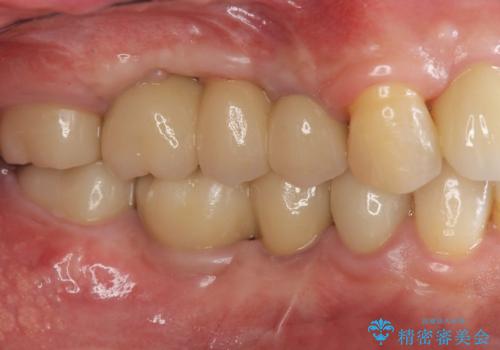

インプラント治療・セラミック治療を含む 全顎的虫歯治療

以上のような問題を、徹底的な虫歯治療、歯周外科、インプラント治療、部分矯正治療、精密根管治療を用いてひとつずつ解決ししっかりと長期的に食事を楽しめるような口腔内環境の再構築を目指します。

セラミック治療の注意事項(リスク・副作用など)

- 天然歯を削ります

- 硬い素材は天然歯を傷つけてしまう場合があります

- かみ合わせや歯ぎしりが強すぎる方はセラミックが割れてしまう可能性があります